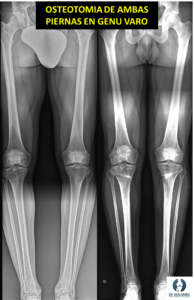

En casos severos o cuando el tratamiento conservador no es efectivo, puede ser necesaria la cirugía. Las técnicas quirúrgicas suelen incluir osteotomías de corrección, lo que quiere decir realizar un corte en el hueso para corregir la desalineación, actuando sobre la zona donde se encuentra la deformidad y colocando el hueso derecho. Para que se mantenga inicialmente esta corrección nos ayudaremos de dispositivos como placas, fijadores externos o clavos, que “sujetaran” el hueso hasta que este suelde.

Además, aplicaremos en ocasiones injertos de hueso, sustitutos óseos y células madre mesenquimales para ayudar en el proceso de cicatrización. La decisión de realizar una cirugía depende de varios factores, incluidos la edad del paciente, el grado de deformidad y la presencia de síntomas significativos.

La cirugía logra la corrección y consolidación ósea en la mayor parte de los casos, aunque hay que saber que el tiempo de recuperación completa es de varios meses. Sin embargo, en pacientes jóvenes es una opción adecuada para evitar la prótesis o retrasar la implantación de esta durante muchos años.